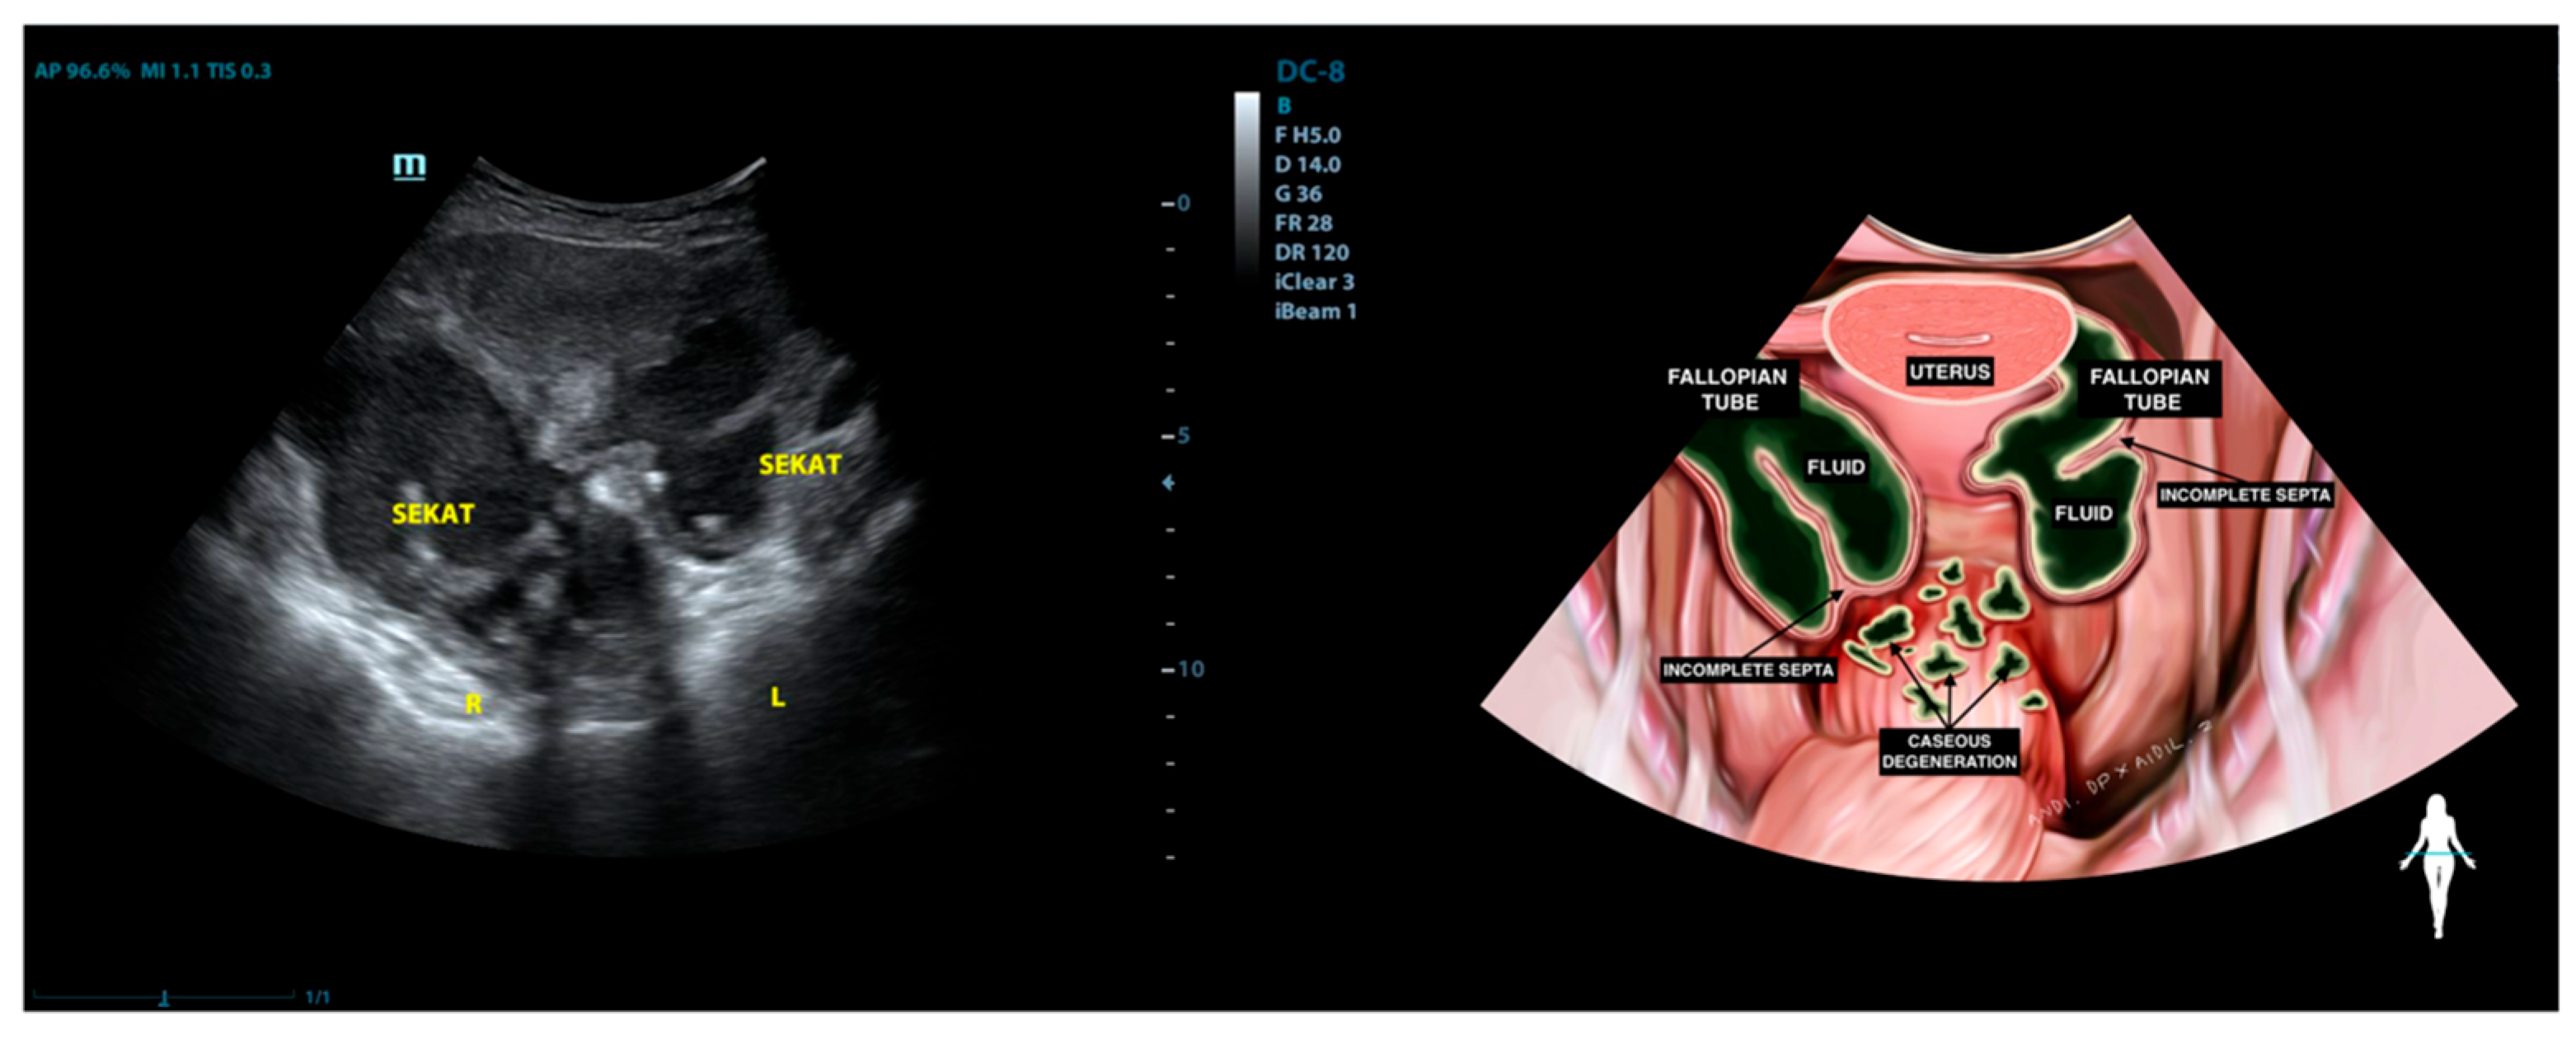

| 6 | STG (53) | Adherent to both masses in the adnexa and the rectosigmoid | Not visualized | Mass with incomplete septation (Hydrosalpinx) | Normal | Mass with incomplete septation (Hydrosalpinx) | (−) | (−) |

| 7 | EF (30) | Normal | Normal | Normal | Normal | Mass with incomplete septation, filled with complex fluid (Hydrosalpinx) | (−) | (−) |

| 1 | LA (25) | Normal | Adhesion complex with hydrosalpinx right fallopian tube | Hydrosalpinx, filled with caseous degeneration inside | Adhesion complex with hydrosalpinx left fallopian tube | Hydrosalpinx, filled with complex fluid | Complex ascites | (−) |

| 11 | Y (30) * | Normal | Adhesion to pelvic wall | Not visualized | Adhesion complex with left fallopian tube | Hydrosalpinx, filled with caseous degeneration inside | Complex ascites | (−) |